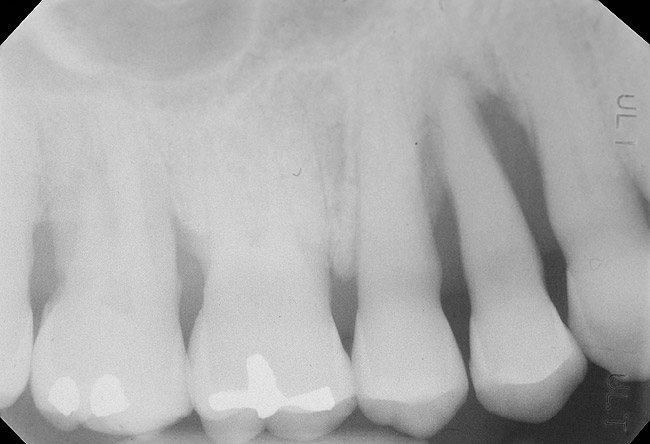

Figure 1  Tooth No. 5 showing advanced periodontal bone loss and a widened periodontal ligament space.

Figure 1

Figure 2  Same case as in Figure 1 after 1.5 years with no treatment. At that time, the bone loss affected the adjacent teeth. The apical extent of the bone loss was approximately 5 mm from the sinus floor.

Figure 2

To meet the needs of the new paradigm, treatment techniques have evolved for bone preservation. Figure 1 shows a case in which tooth No. 5 had advanced bone loss and the treatment option was to save it. The patient did not opt to have this treated, however. Figure 2 shows the same area approximately 18 months later when the advanced bone loss was also affecting the adjacent teeth. Traditional treatment—extraction of this tooth—would have led to a significant hard- and soft-tissue defect. Use of the alternative treatment—grafting of the socket at the time of extraction19,20—preserved the hard and soft tissue (Figure 3 and Figure 4). Grafting the socket to minimize postextraction ridge shrinkage is a much more conservative approach than performing ridge augmentation after extraction,21 which would have been required if the socket grafting had not been done in conjunction with the extraction.